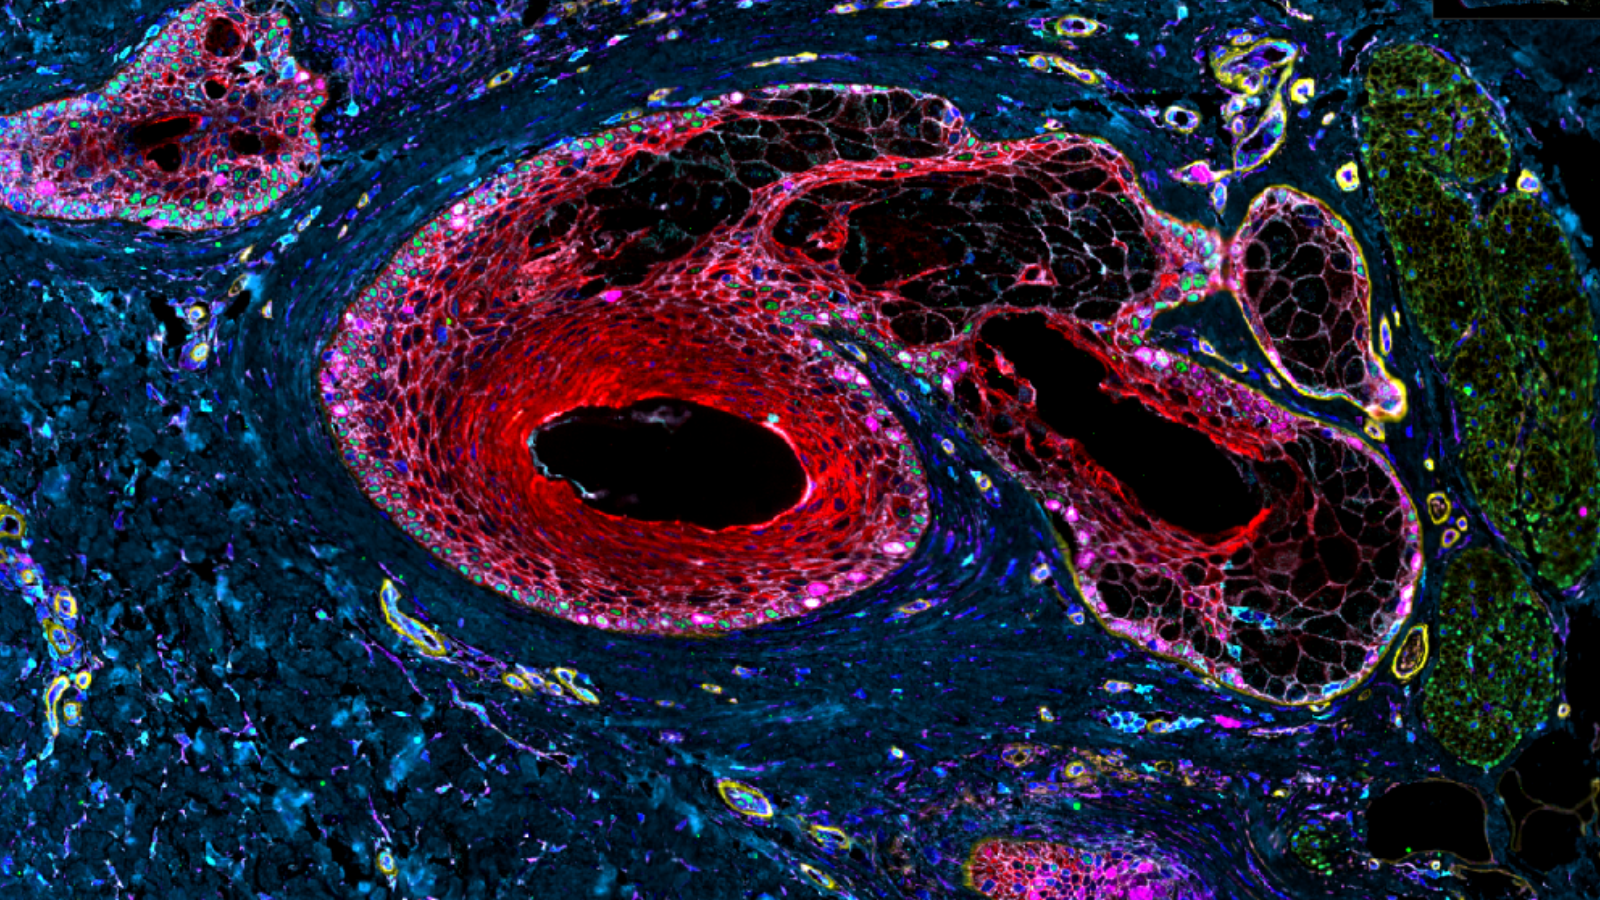

Autofluorescence image capturing heart cells (red), nuclei (blue), and dense fibers of the heart (green), courtesy of Dr. Seth Currlin at University of Florida

An autofluorescence image of cells that make up the heart/cardiac muscle, from Dr. Seth Currlin of University of Florida

The lining of the uterus & fetal cells within & around maternal spiral arteries, courtesy of Dr. Michael Angelo at Stanford